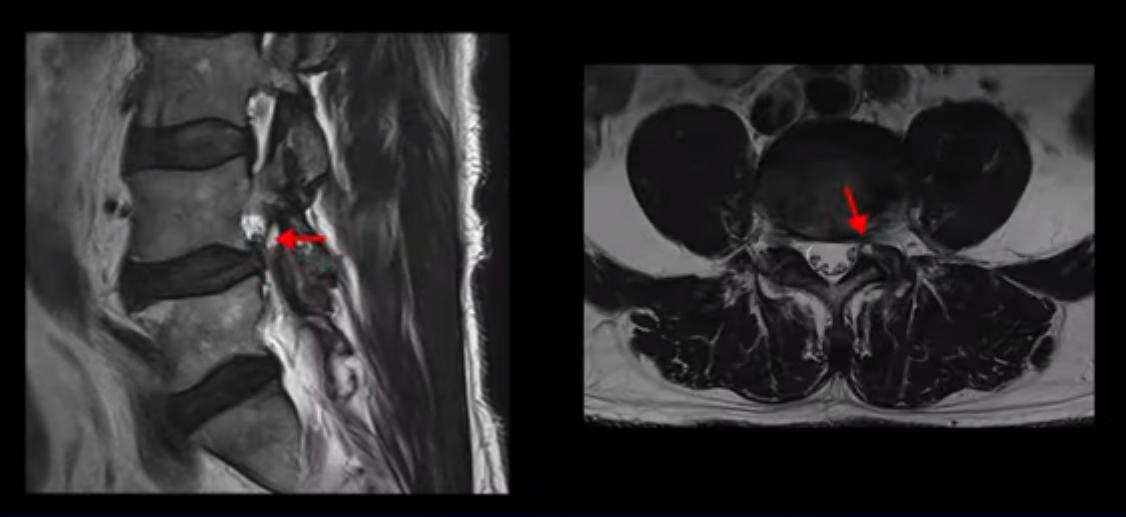

이분 허리 MRI를 보면 60세가 넘었기 때문에 퇴행이 진행은 되었지만 아주 심하지는 않습니다.

이분 왼쪽 다리가 저리고 아파서 2~3년 전부터 걷기가 힘들었는데 이분 허리 4번, 5번 마디에 신경 가지가 빠져나가는 추간공이 다른 마디에 비해서 좁아져 있습니다. 하지만 아주 심하게 좁아져 있지는 않습니다.

의사마다 MRI를 보고 얘기가 달랐다고 하는데 심하지 않다고 하는 쪽이 맞습니다. 그런데 이분은 신경 구멍 넓이에 비해 증상은 매우 심한 편입니다. 왜 그럴까요? 이 이유와 어떻게 치료하는지에 대해 지금부터 설명해 드립니다.

참고로 이분은 처음 병원에 오셨을 때 왼쪽 허리와 엉덩이가 차돌처럼 굳어서 침을 놓아도 침이 잘 꼽히지 않을 정도의 상태였습니다. 이렇게 허리와 주변 근육들이 뭉치고 굳어서 척추를 잡아 당기니까 신경구멍이 조금만 좁아져도 신경 자극 증상을 심하게 느끼는 겁니다. 그럼에도 불구하고 이분처럼 60대 초반의 남자분들은 본인 근육에 문제가 있다는 걸 전혀 인지하지 못하는 분들이 많습니다. 그러니까 신경이 눌렸다고 신경을 어떻게 치료할 지에만 관심을 가지고 신경주사만 맞으면서 이런 근육상태로 근력 운동을 하시는 분들이 많습니다. 통상적으로 이런 근육상태에서 근력 운동을 하면 근육이 더 뭉치고 굳어버리고 따라서 협착증 증상이 악화되는 분들이 많습니다.